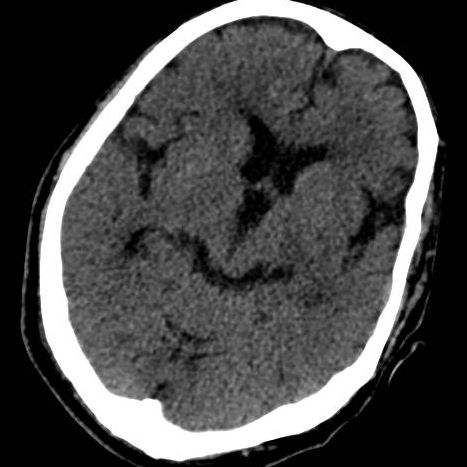

卒中中心迅速反应,启动绿色通道。急诊头颅CT可见脑干梗死灶。患者在静脉溶栓时间窗内,急诊行静脉溶栓,同时急诊头颅MRA可见基底动脉闭塞,DWI上还尚未显影。如果救治不及时,基底动脉闭塞很可能引起脑干、小脑大面积脑梗死从而危及生命。

术后头颅ct未见出血。

术后第三天头颅DWI可见脑干、小脑双侧半球多发急性梗死灶显影,若基底动脉不能及时开通,后果不可想象。